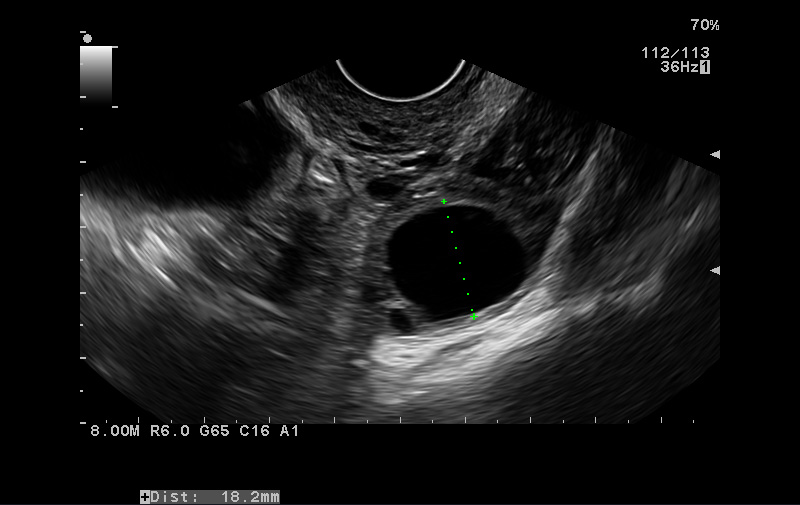

@kristinkaris no ak si videla na sone folikul a máš takéto testy, tak šup na to 🙂 folikul je hladký a jasne ohraničený "kruh" na sone, prasknutý je vidieť tak ťažšie, vyzerá ako taká hviezdička.

@kristinkaris takto vyzerá neprasknutý folikul. Prasknutý je taký zošuverený a v strede má niečo ako hviezdičku. Neviem to lepšie popísať 🙂

@bambulka711 no môj gynekológ ma 70 rokov ale je to kapacita a on teda keď robí sono tak riadne poctivo o tejto doktorke som si myslela že tiež je v pohode no ale po dnešku neviem čo si mám myslieť zvláštne že ho ani len nezmerala lebo to bol jasný kruh